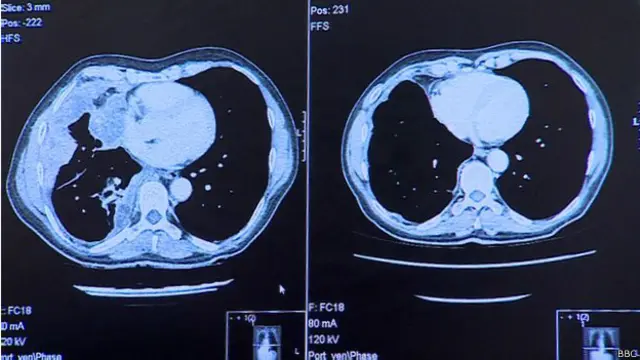

Сканирование (на снимках выше) показало, что после введения всего трех доз препарата метастазы полностью исчезли из легких.